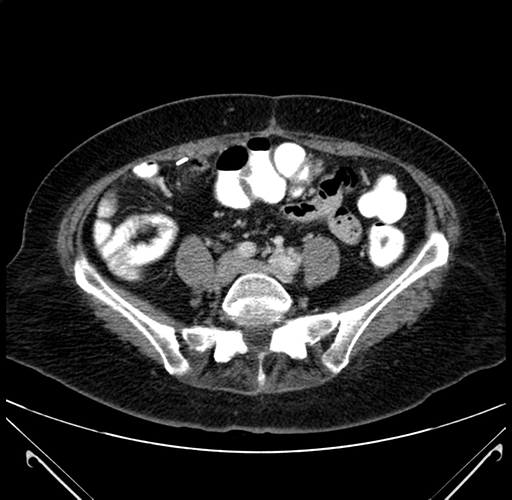

Axial Venous